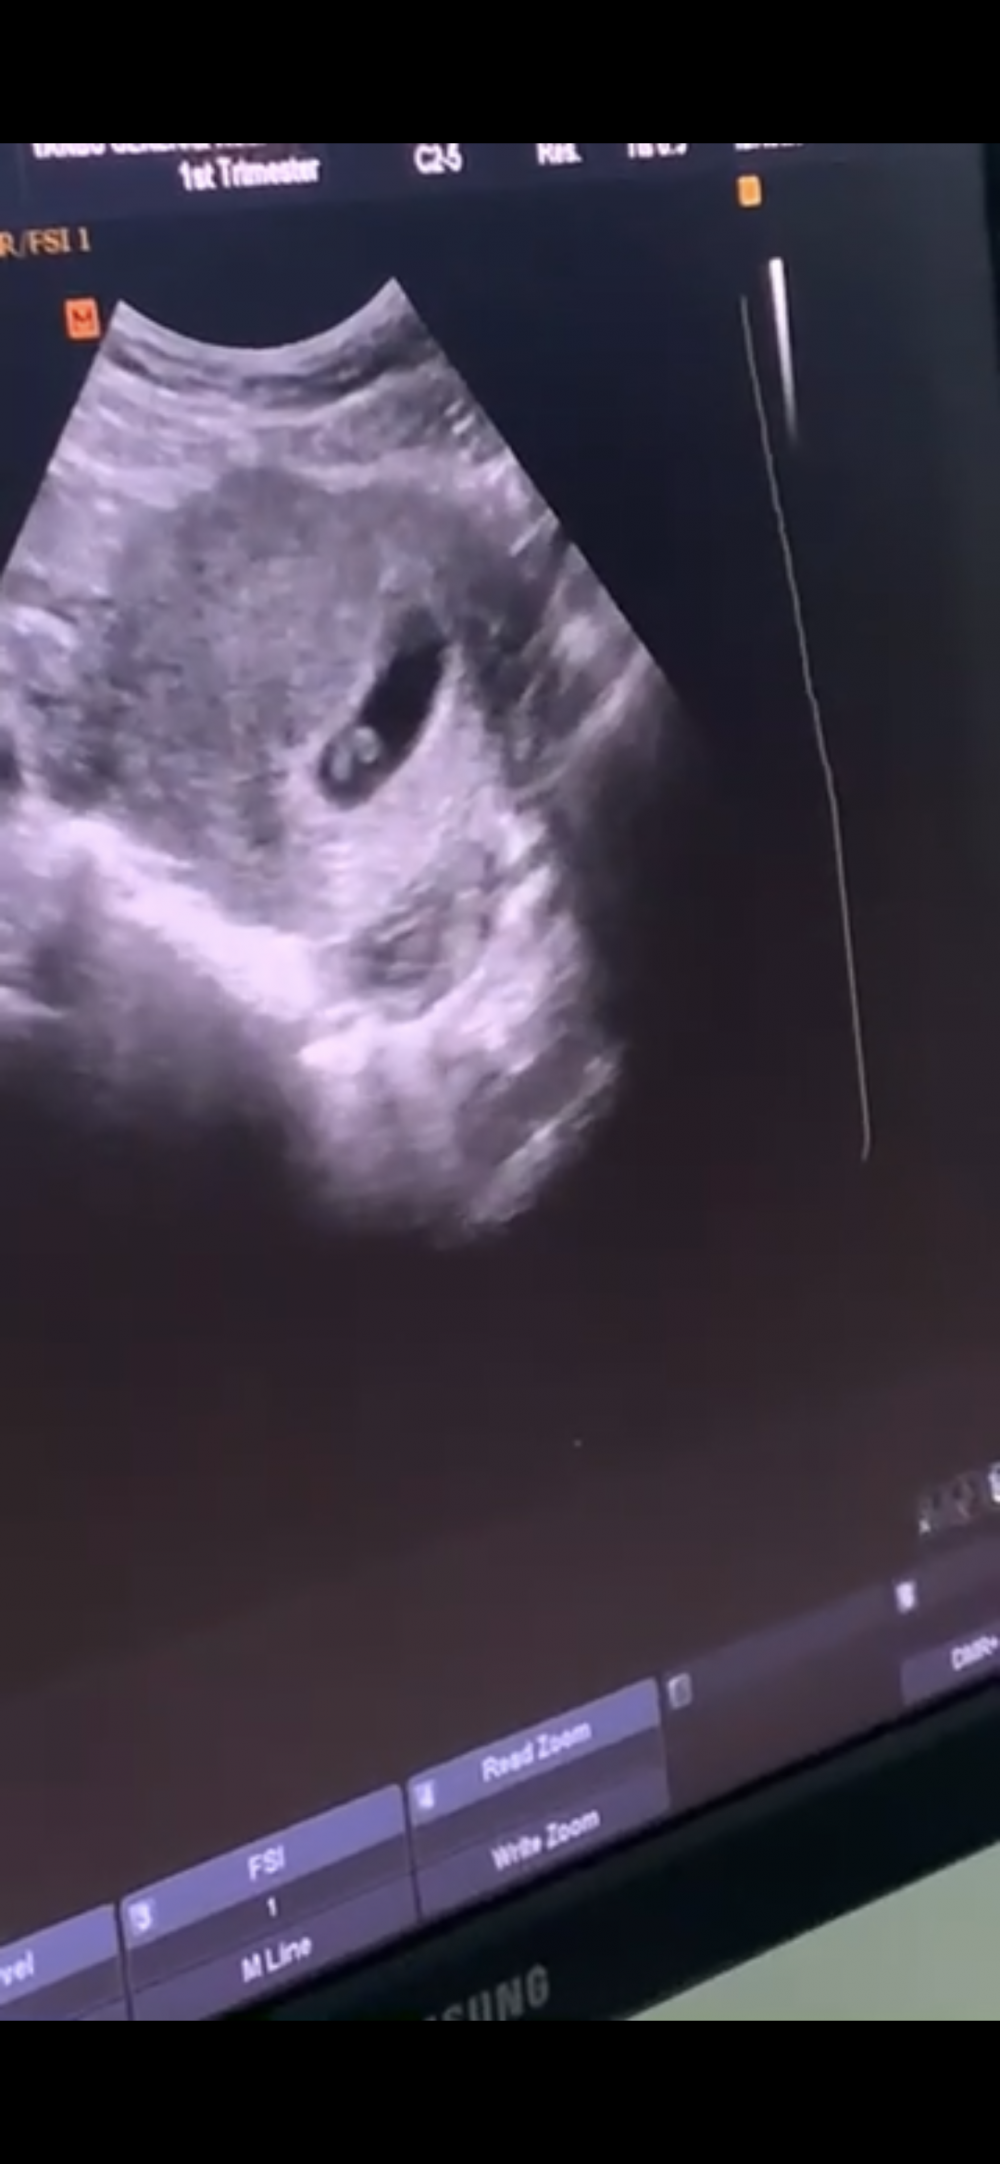

اليوم سويت سونار و عرفت الجنس 😇

طلع ولد 💙